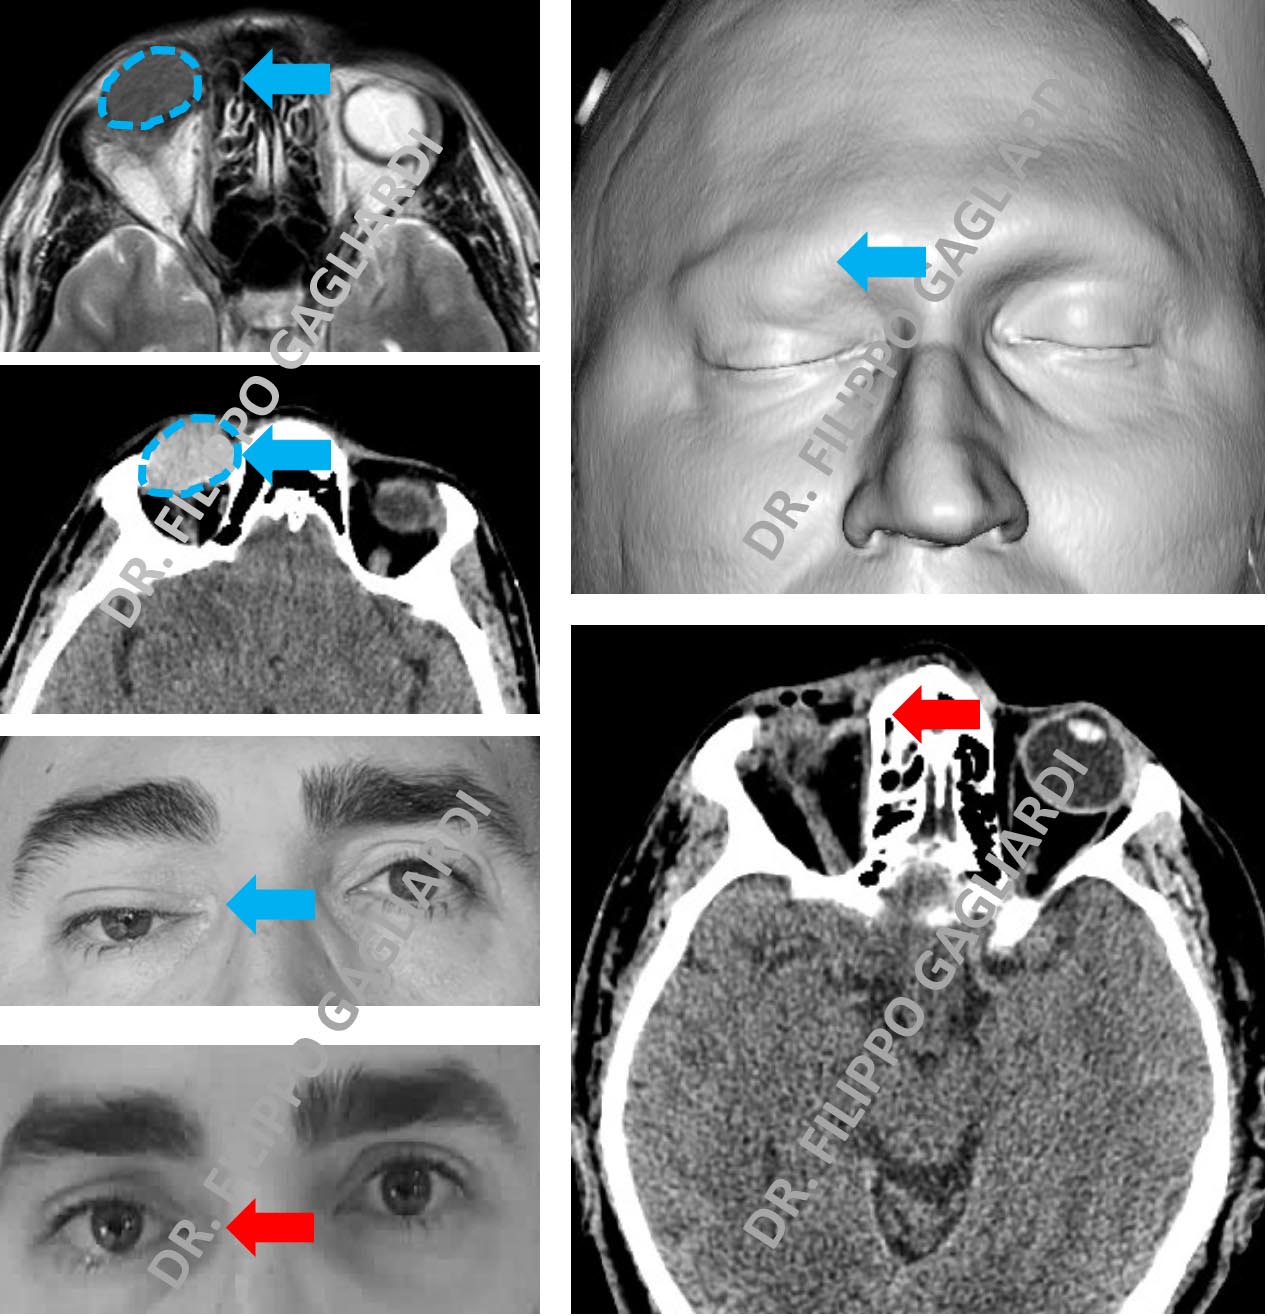

Chirurgia dell'orbita e dei seni paranasali Esempio di chirurgia dell'orbita e dei seni paranasali. Caso di asportazione di una lesione dell’orbita che causava compressione del globo oculare e paralisi della palpebra. Frecce azzurre i reperti prima dell’intervento. Frecce rosse il risultato post-operatorio (immagine gentilmente concessa dal paziente).